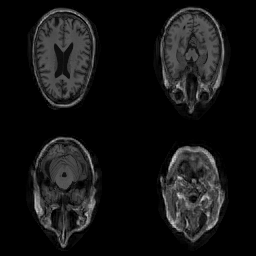

| Original | Renderings after de-identification | Original | MRI slices after de-identification | ||||||

|

![]() |

||||

| CP-GAN | FACE MASK | DEFACE | QUICKSHEAR | CP-GAN | FACE MASK | DEFACE | QUICKSHEAR | ||

Benchmark De-Identification Methods. We compare our result with three publicly available and widely-established methods for de-identification of MRI head scans, depicted in Figure 3. All methods have in common that they (1) are not deep-learning-driven, (2) require no additional training and (3), are used on a day-to-day basis in neuroscience and clinical research. All procedures were applied with default settings on images of resolution . The methods include QUICKSHEAR [Schimke et al.(2011)Schimke, Kuehler, and Hale], FACE MASK [Milchenko and Marcus(2013)], and DEFACE [Bischoff-Grethe et al.(2007)Bischoff-Grethe, Ozyurt, Busa, Quinn, Fennema-Notestine, Clark, Morris, Bondi, Jernigan, Dale, Brown, and Fischl]. Descriptions of the methods are provided in the Appendix. We also include MRI WATERSHED [Ségonne et al.(2004)Ségonne, Dale, Busa, Glessner, Salat, Hahn, and Fischl], a skull-stripping method that removes everything except the brain.